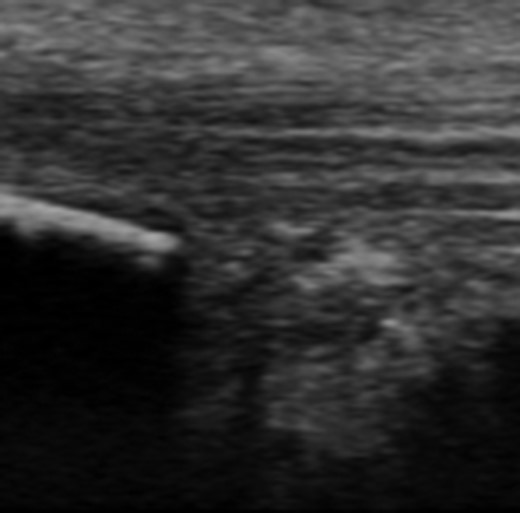

Dynamic ultrasound examination of the left heel showed a diffusely thickened subcutaneous bursa, with fluid-rich islands. Regions of high blood flow were seen in the bursal walls. There was tendinopathy in the distal Achilles, which measured 6–7 mm in thickness with intra-tendinous bone formations and calcification, but no high blood flow. Finally, there was a minor Haglund-like deformity with a sharp edge and a slightly enlarged retrocalcaneal bursa with the appearances of scar tissue formation, but no fluid or increased blood flow. There were no signs of partial ruptures in the distal part of the Achilles. These ultrasound findings were consistent with those of a previous MRI (Figs 1–5).

Ultrasound image of diffusely thickened subcutaneous bursa and underlying intra-tendinous bone formations.